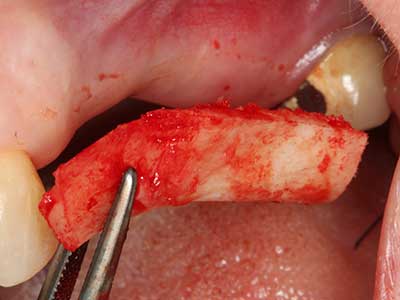

Фиг. 3: Базалното разделяне на блока е по-лесно със специалните извити накрайници.

Пиезохирургията има допълнителни предимства при събиране на костни блокове. В допълнение към високата прецизност при остеотомията, описана по-горе, употребата на фините режещи накрайници значително намаляват загубата на материал. Голяма загуба на материал по време на събиране може да се очаква с дебелите накрайници, особено при употреба на борери Линдеман (Lakshmiganthan, Gokulanathan et al. 2012). Базалното разделяне, което е необходимо, особено за присадка на блок при ретромолар, е улеснено от специално създадени правоъгълни триони. В резултат на това, пиезохирургията е разглеждана като прецизна, улеснена и безопасна процедура за събиране на костни блокове в ретромоларното пространство (Happe 2007) (Фиг. 1-12).